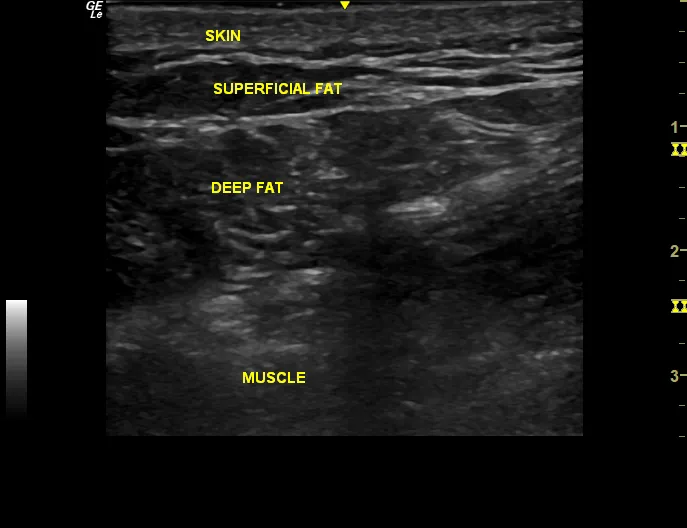

Shoulder rotator cuff tears and elbow tendons that cause tennis and golfer’s elbow are often caused by tendon degeneration. In adults over 40 years old, tendons don’t heal at local regeneration is poor without help. PRP (platelet rich plasma) is an excellent treatment producing healing of the degenerated tendon fibers including those that may may include tiny tears. Unfortunately partial